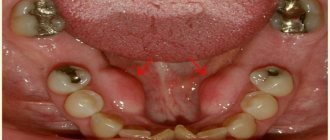

Photo: cervical lymphadenitis